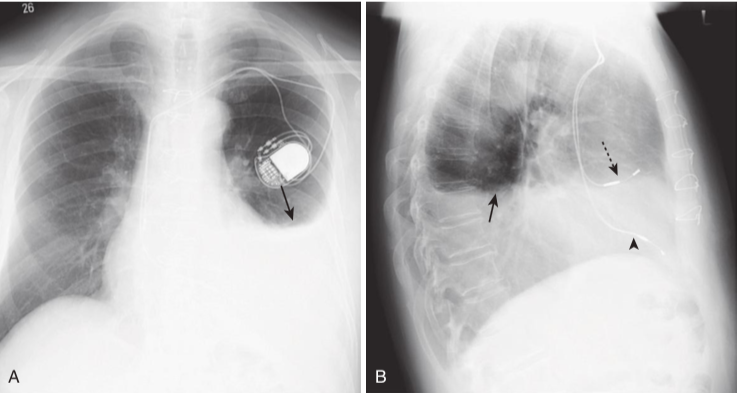

Dressler syndrome (postpericardiotomy/postmyocardial infarction syndrome).

There is a left pleural effusion present (solid black arrows in A and B). This syndrome typically occurs 2 to 3 weeks after a transmural myocardial infarct. It also can occur following pericardiotomy, such as that which occurs in patients undergoing coronary artery bypass surgery, as in the case shown here. The combination of chest pain and fever, left pleural effusion, patchy left lower lobe airspace disease, and pericardial effusion several weeks following a myocardial infarction or open-heart surgery should suggest the syndrome. It usually responds to high-dose aspirin or steroids. This patient has a dual-lead pacemaker in place, and on the lateral projection (B), the leads are seen in the region of the right atrium (dotted black arrow) and right ventricle (arrowhead)